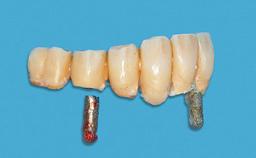

Four Immediately Loaded Mini-Implants Supporting a Mandibular Overdenture

A 74-year-old male patient, a non-smoker, who had been wearing complete dentures for more than 30 years, presented to our clinic complaining about discomfort in connection with his lower denture. The patient suffered from asthma and had a history of cardiac disease and blood pressure disorders. All conditions were medically controlled and stable. The clinical inspection of the oral cavity revealed an ill-fitting complete mandibular denture. The patient expressed the wish for his lower denture to “stop moving when chewing, swallowing, and speaking.” He reported having heard about dental implants and asked whether these could help in “fixing” his lower denture, but also requested non-invasive treatment. The mucosa presented healthy and was free of defects such as pressure sores. An band of keratinized mucosa approximately 2 mm wide was visible. The patient’s mucosal biotype was medium thick to thin.

# of Implants 4

Type of Implants One-Piece|Reduced-Diameter